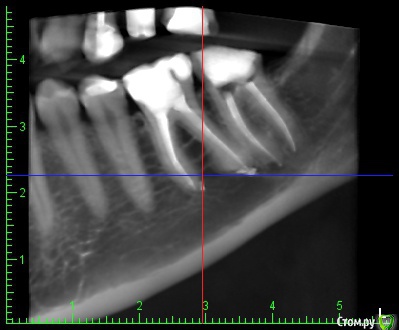

inSight Опубликовано 12 февраля, 2017 Поделиться Опубликовано 12 февраля, 2017 смотреть за динамикой. Неужели эту боль придумывает голова? У меня уже сил нету это терпеть. До лечения ведь вообще ничего не болело. Тянет-распирает-ноет-давит преимущественно снизу в районе 36 и 37 зуба. Но как его раскрывать, когда откуда-то идёт давяще-ноющее-распирающее ощущение? я затрудняюсь ответить, не нравится мне ваш 27 зуб смотрю кт и вот не пойму толь пропущенная анатомия. Нужна помощь более опытных. Ссылка на комментарий

inSight Опубликовано 14 февраля, 2017 Поделиться Опубликовано 14 февраля, 2017 Вродеб нормально. Апну тему. http://s011.radikal.ru/i315/1702/ce/2415863cdd83t.jpg http://s42.radikal.ru/i096/1702/76/855feb5eec66t.jpg http://s019.radikal.ru/i639/1702/15/7b20e47e5e0dt.jpg http://i062.radikal.ru/1702/b5/957a4094f4bet.jpg Ссылка на комментарий